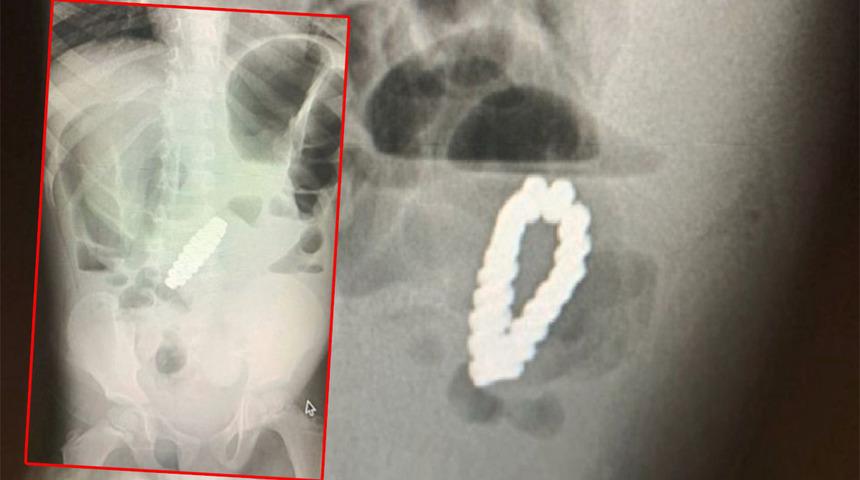

Amerika Birleşik Devletleri’nde yaşayan 4 yaşındaki ismi açıklanmayan bir erkek çocuğu şiddetli karın ağrısı nedeniyle hastaneye kaldırıldı. İki gün boyunca karın ağrısı, kusma ve kabızlık çektikten sonra hastanede tedavi altına alınan küçük çocuğun cerrahi operasyonla apandisiti alındı. Ancak yapılan taramalarda çocuğun midesinde metal boncuklardan oluşan bir bilezik olduğu tespit edildi.

Genellikle ağrıyı hafifletmek için kullanılan manyetik bilezikler özellikleri nedeniyle içeride halka oluşturacak bir biçimde birbirlerine yapışmıştı.

Bilezik çocuğun bağırsaklarına doğru hareket ederek organlarında delik açılmasına neden olunca doktorlar laparotomi yaparak 18 altıgen şeklinde boncuğu çıkartmak için cerrahi operasyona başladılar.